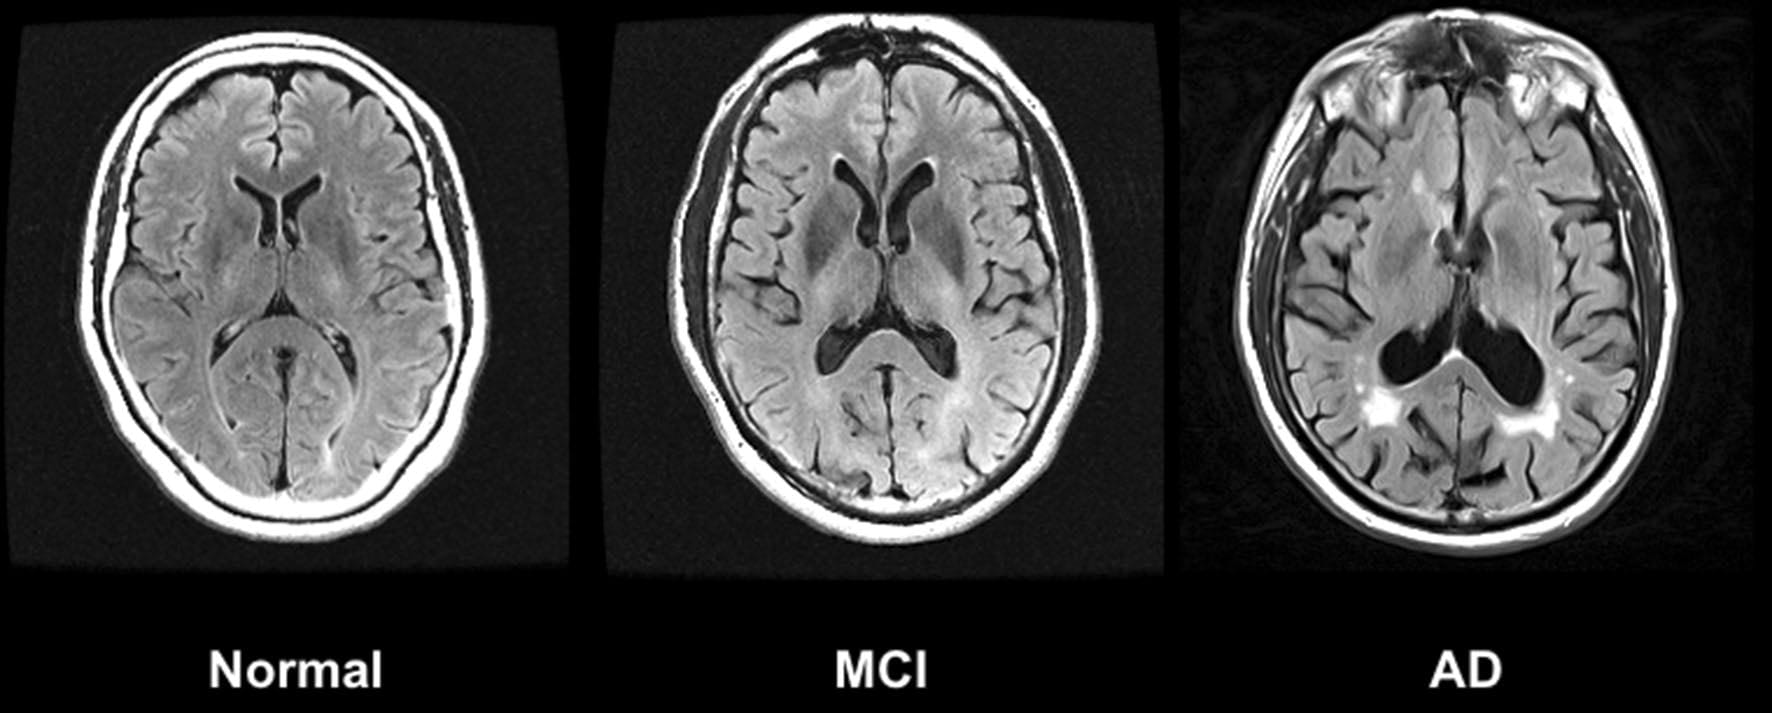

Both drugs have been viewed by researchers as a potentially big step forward in the fight against Alzheimer’s, as they target known causes of the disease rather than just tackling symptoms like most drugs currently available on the market. Donanemab works by binding to amyloid — one of the proteins, along with tau, that is associated with Alzheimer’s disease — to clear buildup in the brain. Although not a cure, the drug has been shown to slow the progression of cognitive decline in patients with Alzheimer’s disease.